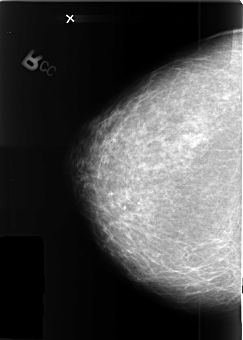

B_3410_1.RIGHT_CC

RIGHT_CC LINES 4080 PIXELS_PER_LINE 2912 BITS_PER_PIXEL 12 RESOLUTION 50 NON_OVERLAY